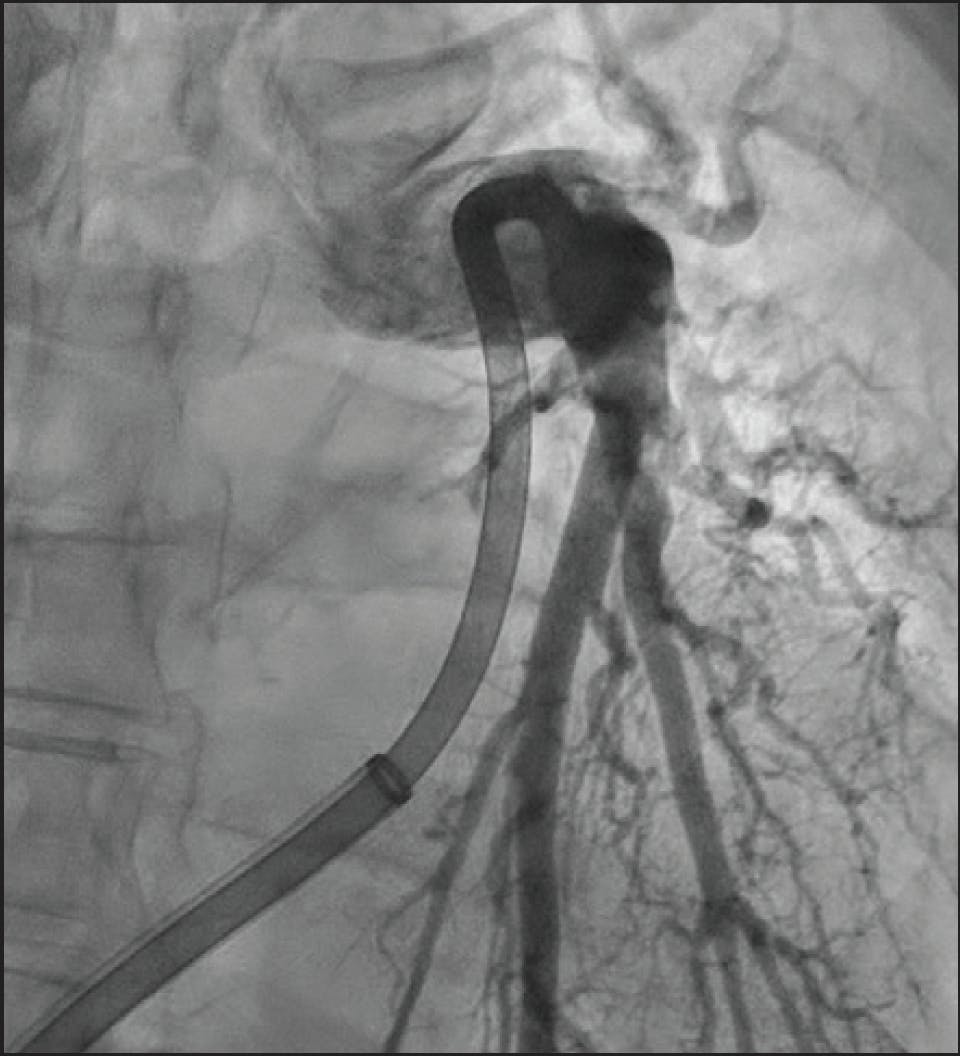

Vascular access was obtained via ultrasound-guided micropuncture of the right common femoral vein, followed by placement of a 7-F sheath. A pigtail catheter was used to obtain baseline hemodynamics, and an inferior vena cavagram excluded right iliac or inferior vena cava thrombus. Initial hemodynamics showed a PAP of 52/23 mm Hg (mean, 35 mm Hg), a mixed venous oxygen saturation of 55.6%, and a decreased cardiac output of 4.27 L/min.

Pulmonary angiography demonstrated extensive thrombus in the left main PA and moderate distal thrombi in the right PA (Figure 3). The access site was preclosed with one Perclose ProGlide device (Abbott), and the sheath was upsized to a 16-F Gore DrySeal Flex introducer sheath (Gore & Associates) after serial dilation. A long J wire was advanced into the right PA, followed by introduction of the CAT16 aspiration catheter. After wire removal, CAVT was initiated, and multiple passes in the left PA extracted a significant amount of thrombus (Figure 4). Postthrombectomy angiography revealed marked reduction in clot burden (Figure 5). The total case time was 45 minutes, with a 3-minute device time using Lightning Flash 2.0. Final hemodynamics showed a PAP of 41/19 mm Hg (mean, 28 mm Hg). The 16-F sheath was removed, and hemostasis was achieved with one Perclose ProGlide.

Figure 3. Initial angiogram revealing extensive thrombus in the main PA.

Figure 5. Postthrombectomy angiogram revealing significant reduction in clot burden.